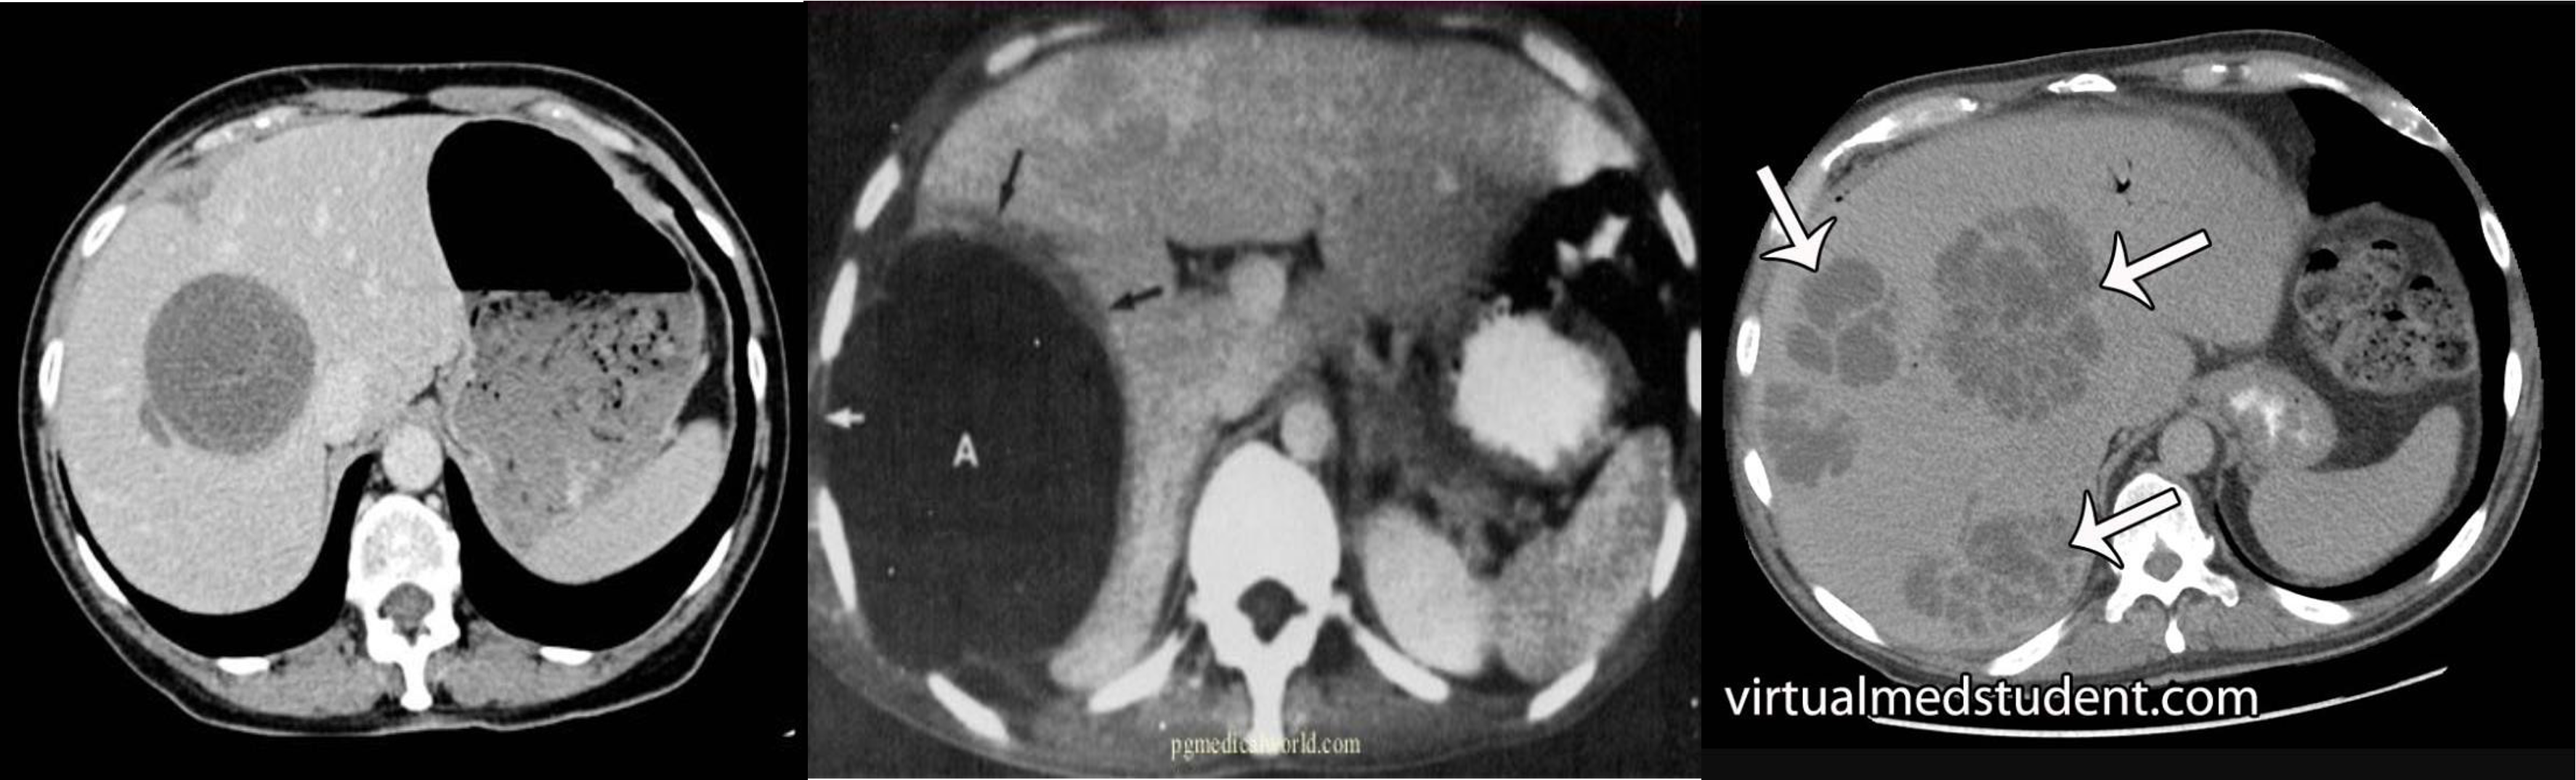

multiple lesion in liver due (Diff; cancer, multiple abcess pyogenic most likely)

Ireggular lesion peripheral enhancement - hypo in cent - febrile tender (liver abcess) - antibiotic + ct u/s guidance drainage

HCC, Cancer of liver, hepatic adenoma, FNH (with central scar star like)

- ct scan (hypodense lesion in liver well circumscribed single - most likely amoebic liver abcess)

- multiple … metastasis